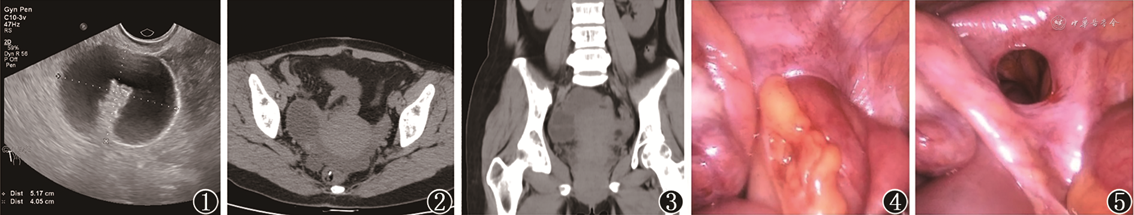

患者女,44岁,因腹痛1 d入院。伴呕吐1次,无腹胀,无肛门停止排气排便。查体:右下腹触及一5 cm × 5 cm大小包块,压痛阳性。实验室检查:白细胞10.8 × 109/L。患者既往2次分娩史,10余年前有剖宫产史,术后恢复可。急诊经阴道超声检查示盆腔右卵巢外侧方见52 mm × 41 mm液性暗区,壁厚,考虑扩张肠管可能(图1)。腹部CT示右侧附件区约47 mm × 35 mm类圆形囊性灶,周围脂肪间隙欠清,盆腔见不规则片状积液;盆腔小肠稍扩张积液(图2、3)。急诊行腹腔镜下探查术,术中见盆腔内约50 ml淡血性液,右侧子宫阔韧带见一3 cm × 3 cm缺口,部分小肠嵌顿其内,血供基本正常(图4、5),左侧卵巢表面见0.5 cm × 0.5 cm子宫内膜异位结节。完整牵拉出阔韧带内嵌顿小肠,血供颜色正常。术后诊断:子宫阔韧带疝。该患者术后恢复良好,术后4 d出院。

子宫阔韧带疝是一种罕见腹内疝[1]。由于其临床症状及影像学表现缺乏特异性,术前诊断困难。患者最常见的症状为机械性肠梗阻症状,如恶心、呕吐、腹胀等,其次是单纯性腹痛。本例患者因右下腹痛及阴道出血就诊,超声检查提示盆腔偏右侧囊性包块;CT提示右附件区类圆形囊性灶、盆腔积液、盆腔小肠稍扩张;经急诊腹腔镜探查术确诊右侧子宫阔韧带疝。